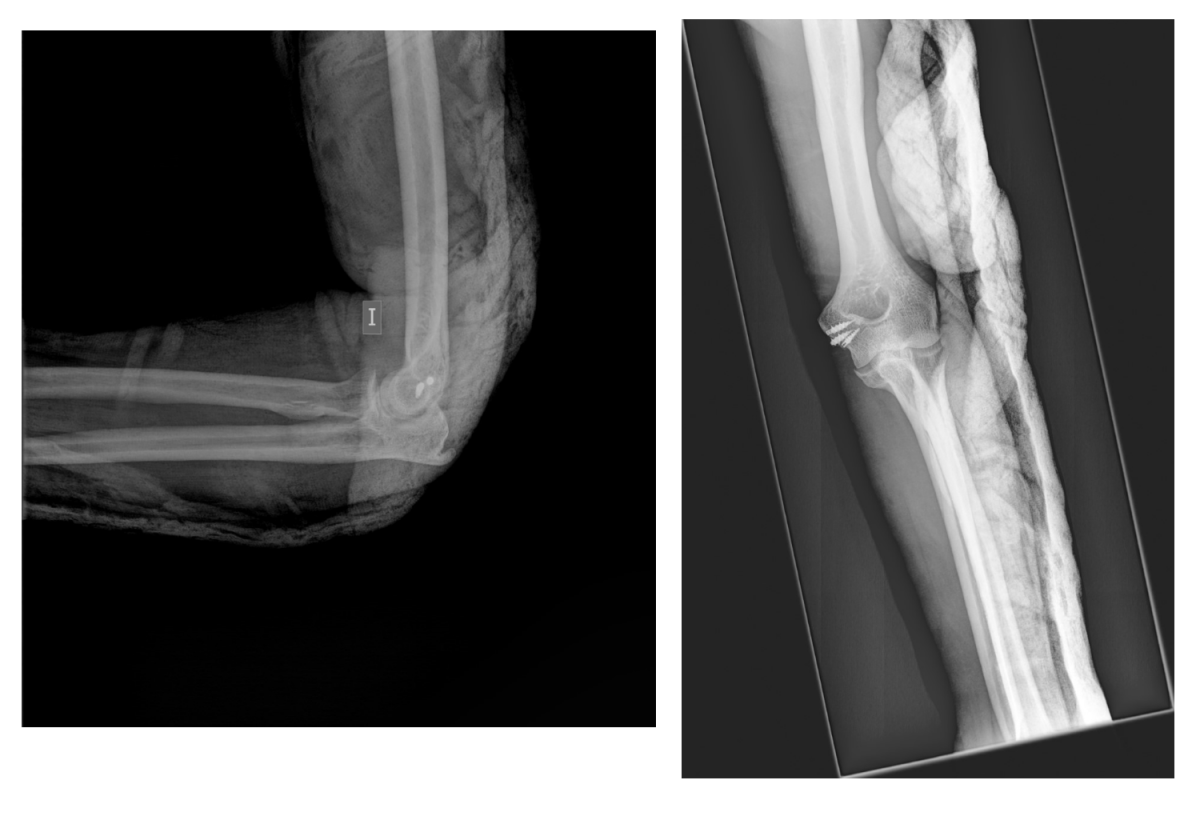

Se trata de un paciente de 61 años de edad que sufrió una luxación de codo izdo, tras caída desde una altura, en marzo del 2018. Tras la reducción de la luxación, se constató un codo inestable por arrancamiento del Lig. Colateral Medial y del tendón conjunto de la musculatura flexora-pronadora. El paciente fue intervenido a la semana del accidente, procediendo a la reinserción y reparación del complejo ligamentoso y tendinoso mediante anclajes óseos.

Tras 2 meses de la artrolisis, y 6 meses desde el accidente, el paciente tuvo que pasar de nuevo por quirófano, y procedimos a la liberación del nervio cubital en el canal epitrócleo-olecraneano, con disminución posterior de la clínica, pero sin resolución completa.